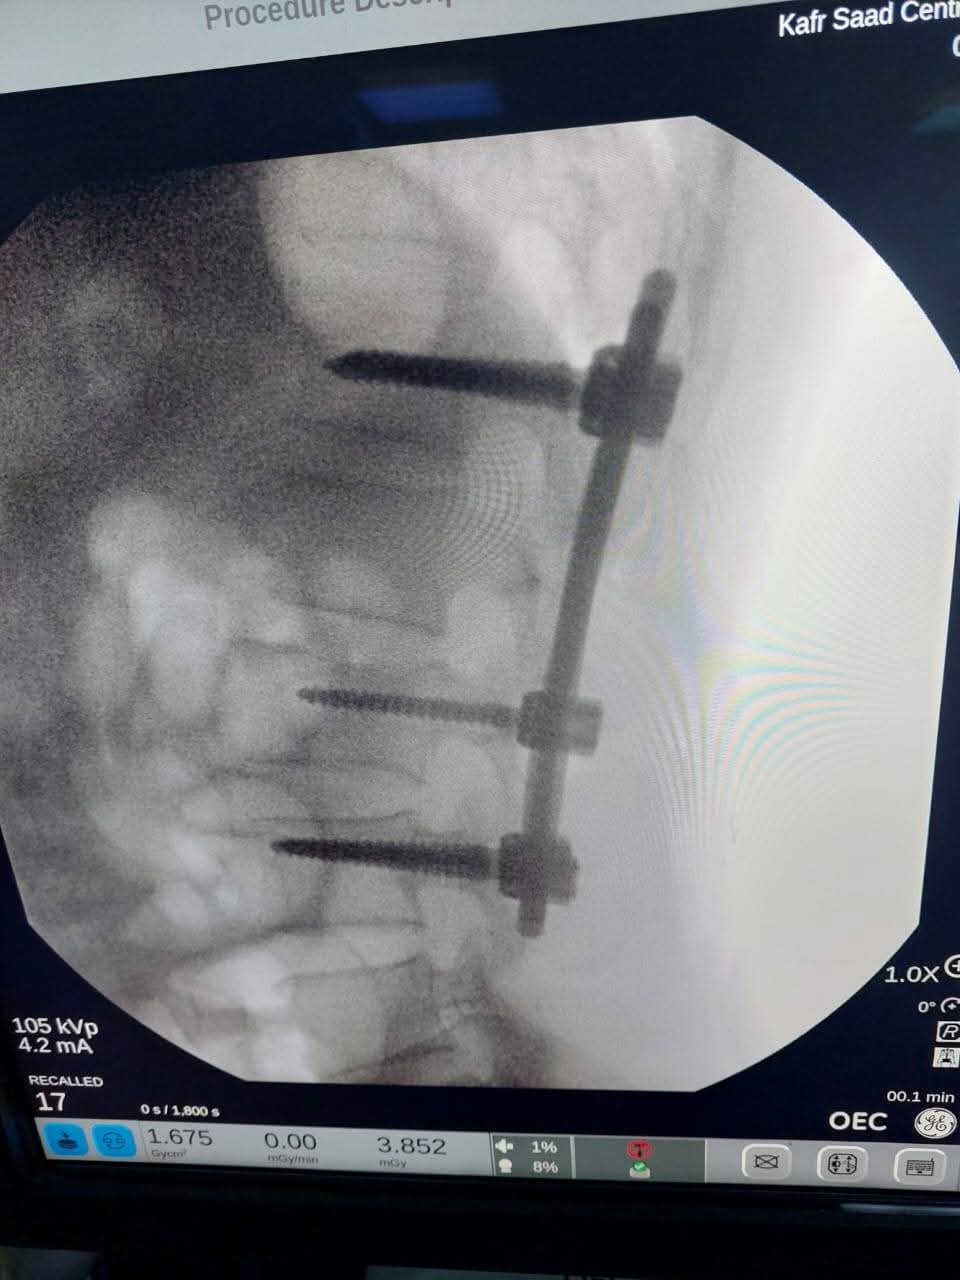

وفي سياق متصل، أكد الدكتور محمد بدران، مدير مديرية الصحة بدمياط، أن المستشفى استقبلت المريض بعد تعرضه لإصابة أثناء نزوله من القطار، حيث أصيب بكسر في الفقرات القطنية. وأوضح أنه تم إجراء الإسعافات الأولية للمريض، ثم تم تجهيز الحالة لإجراء العملية التي تكللت بالنجاح. تم تثبيت الكسر باستخدام المسامير والأعمدة الطبية، مع متابعة مستمرة لحالة المريض بعد إجراء الجراحة.